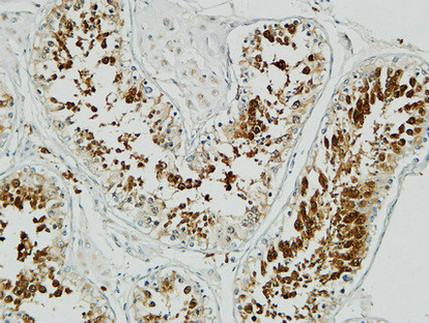

Op18 Polyclonal Antibody

| WB, IHC-P, IF, ICC, E |

| Dilution | WB~~Western Blot: 1/500 - 1/2000. Immunohistochemistry: 1/100 - 1/300. Immunofluorescence: 1/200 - 1/1000. ELISA: 1/10000. Not yet tested in other applications. IHC-P~~Western Blot: 1/500 - 1/2000. Immunohistochemistry: 1/100 - 1/300. Immunofluorescence: 1/200 - 1/1000. ELISA: 1/10000. Not yet tested in other applications. IF~~1:50~200 ICC~~N/A E~~N/A |